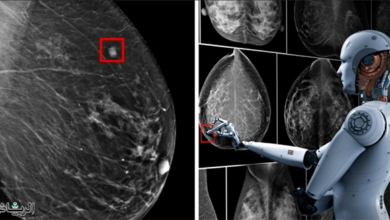

الذكاء الاصطناعي يساعد في تشخيص سرطان الثدي

الذكاء الاصطناعي يساعد في تشخيص سرطان الثدي كشفت دراسة علمية أجريت في السويد أن منظومات الذكاء الاصطناعي يمكنها أن تساعد…